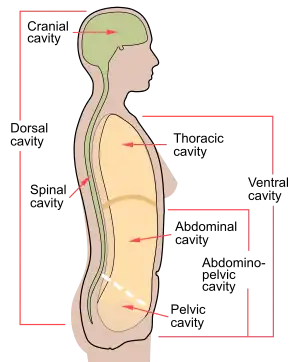

The various cavities of the human body as seen in a lateral projection, with the pelvic cavity labeled 4. | |

Female pelvic cavity Lateral projection of the human body cavities, with the line separating the abdominal and pelvic cavities shown.

Lateral projection of the human body cavities, with the line separating the abdominal and pelvic cavities shown.